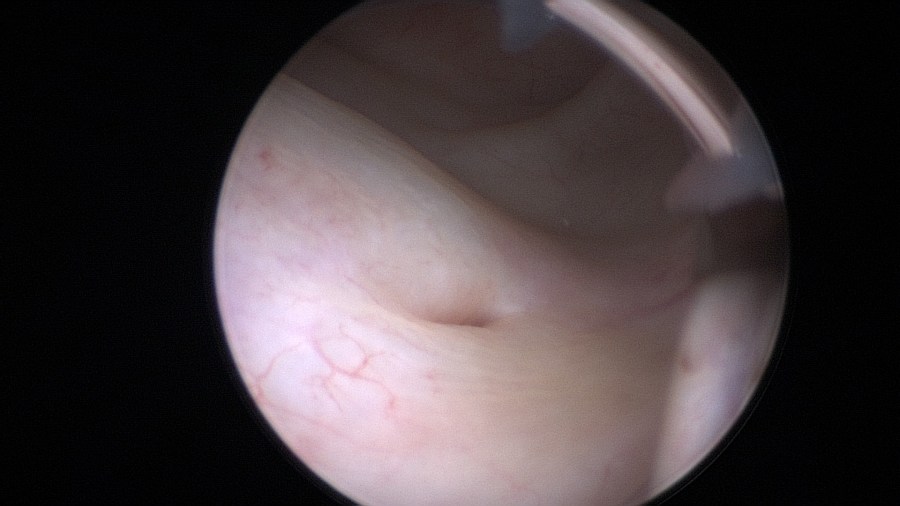

Pushing the needle forward up to the second marking (2cm mark) gives you perspective of actual distance.

By retracting the cystoscope you can perform an accurate measurement – estimate of the urethra.

The right height to insert the needle is at least 2cm from the bladder neck. This is because after inserting you push the needle up to the first mark (1cm). In other words you are placing the depots 1cm higher than the actual location of the cystoscope.

Start on the 12 o’clock position and gently press the cystoscope against the anterior urethral wall while making sure its axis remains parallel to the urethra. This will create a small “mucosal shelf”, in which the needle can vertically penetrate the urethra.

The bevel of the needle should be facing towards the center of the lumen.

Insert the needle up to the 1cm mark.